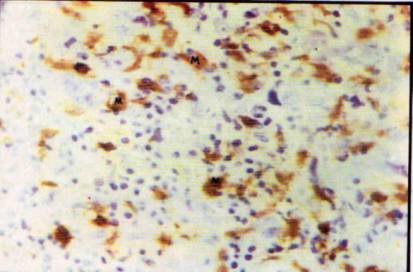

Foto

11: Estructura venular de pared endotelial gruesa (V) con linfocitos que

atraviesan

12: Abundantes mastocitos concentrados en el estroma modificado peritumoral (M)

13: Estroma conectivo y neovascular con discreto infiltrado por células

14: Con fondo de infiltrado leucocitario mononuclear neovasos, se observan macrófagos

cargados de pigmento hemosiderinico (M) y células plasmáticas maduras (P)

Los neovasos presentaron en áreas aparentemente más antiguas, paredes

delgadas y tejido conectivo hialino perivascular, adoptando además la foriria

de lagos extensos y delgados interconectados (foto 13).

Algunas áreas del sector fibroso limitante mostraron además de la

presencia de macrófagos con restos fagocíticos de hemosiderina, la afluencia

de algunos plasmocitos con evidencias de marcada actividad secretoria y

disposición foca] agrupada (foto 14).